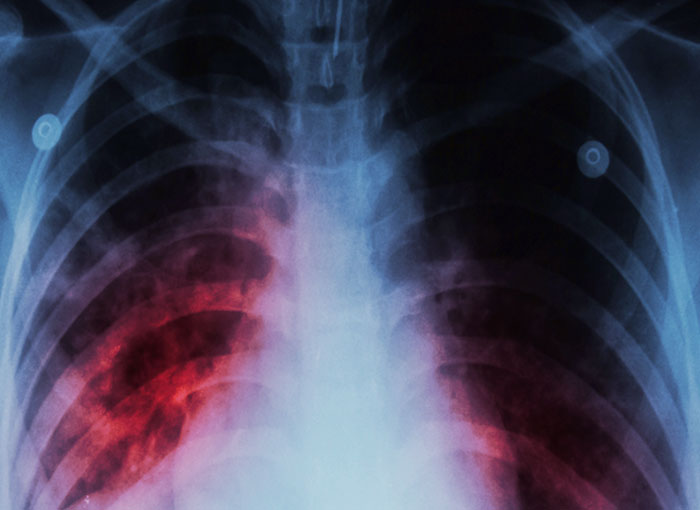

טיפול קשה וממושך, אבל בלעדיו רבים מהחולים ימותו. צילום רנטגן של חזה של חולה שחפת | צילום: Shutterstock